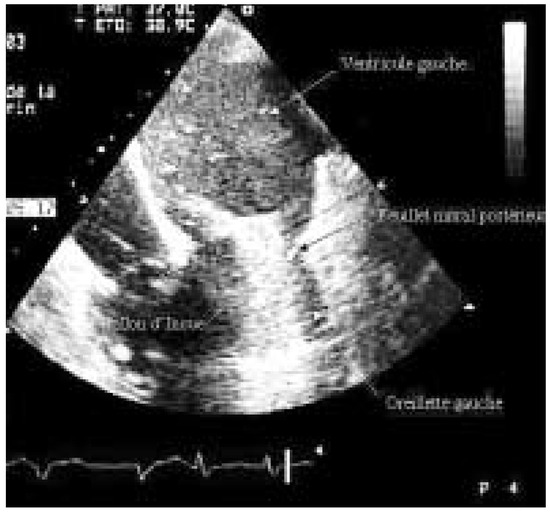

The definition of metabolic syndrome includes the presence of at least three of the following criteria: dyslipidaemia, hyperglycaemia, hypertension, and obesitas. The risk for cardiovascular events is strongly elevated in patients with metabolic synd...